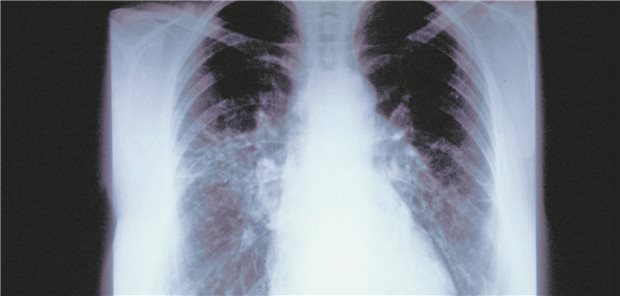

Die neue Version der Living-Guideline zum Bronchialkarzinom enthält zahlreiche Änderungen: Unter anderem zu den verschiedenen Krankheitsstadien – sowie ein eigenes Kapitel zum Lungenkrebs-Screening.